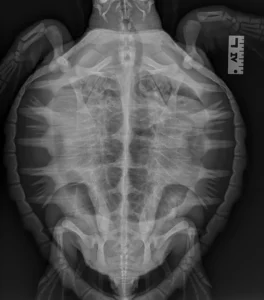

The sea turtle’s carapace, or hard upper shell, provides this salty swimmer with protection, buoyancy, and the ability to move through the water with little effort. This vital structure is made of flattened bones covered in horny plates called scutes. The carapace is part of the sea turtle’s skeleton, forming the rounded top and flat underside and connected to the turtle’s body by a series of bony bridges. As the turtle grows, its carapace grows, too.